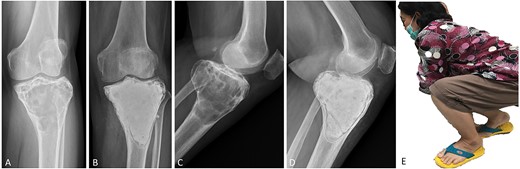

(A, C) Case no. 7: female, 54 years of age with GCTB at the proximal tibia with subchondral bone involvement, Campanacci grade III. (B, D) Radiograph at 58 months after extended curettage with hydrogen peroxide, phenol, and cementation. (E) MSTS score 86%.

Surgical procedures were performed by two orthopedic oncology surgeons using the same surgical technique. In all cases, GCTB was confirmed by clinical data, plain radiography and magnetic resonance imaging (MRI), as well as histopathologic examination before and after surgery. Whether a medial or lateral approach was employed depended on tumor location. A large cortical window equal in size to the tumor area was created to provide visualization of the entire tumor cavity, and intralesional curettage of the tumor was performed. If the tumor extended into the soft tissue, the entire pseudo-capsule was dissected circumferentially and excised. A high-speed burr was used to extend the cavity by at least 2 mm to remove the residual tumor in all cases except those in which the lesion was in subchondral bone and cartilage. Hydrogen peroxide is the preferred local adjuvant agent at our institution, but phenol was applied along the cavity wall using gauze in three cases, and argon beam coagulator was applied in six. After the application of local adjuvant, the irrigation cavity was rinsed with saline solution. If the tumor involved subchondral bone or cartilage, hydroxyapatite bone substitution was applied 5–10-mm above subchondral bone to prevent complications from allograft and donor-site morbidity of the autogenous bone graft. We defined subchondral bone involvement as tumor location <5 mm from joint cartilage. Every part of the remaining cavity was filled with PMMA without implant augmentation or internal fixation (Figs 1–4). The large cortical window was left open with cement in most of the cases in which the cortex was destroyed by the tumor.